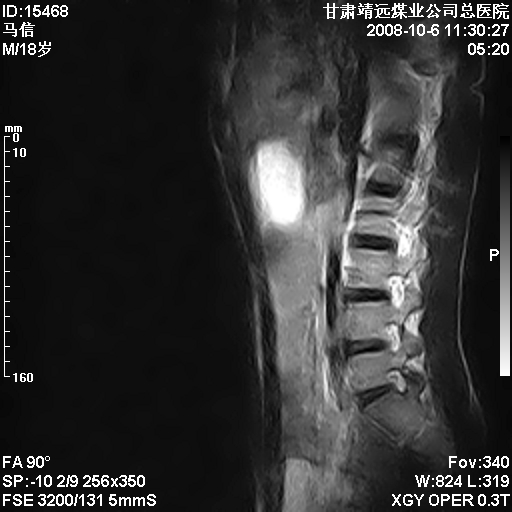

患者18岁,学生,在玩耍中受伤来检查,患者喜欢打篮球。颈椎内异常信号影,我们考虑占位,但是不像占位,又考虑硬膜囊的增厚,大家关建看颈椎椎管内的那个异常占位信号

腰椎的改变是不是正常发育的改变,还是打篮球的长期慢性损伤。

考虑 c3-4 c4-5 c5-6椎间盘突出,l3-4 l4-5 l5-s1椎间盘变性

颈椎建议做增强扫描;腰椎诸椎终板骨骺炎。

脑脊液流动伪影?

后纵韧带增厚,颈2/3、3/4、4/5、5/6椎间盘变性、突出;椎体有旋转,提示椎小关节有问题;腰椎间盘变性,许莫氏结节。

后纵韧带增厚,颈2/3、3/4、4/5、5/6椎间盘变性、突出;椎体有旋转,提示椎小关节有问题。腰椎诸椎体终板骨骺炎可能性大!支持!

是正常的脑脊液波动伪影

脑脊液流动伪影

你说的占位是伪影。在我们医院1.5t和3.0t的mr上是经常看见的。